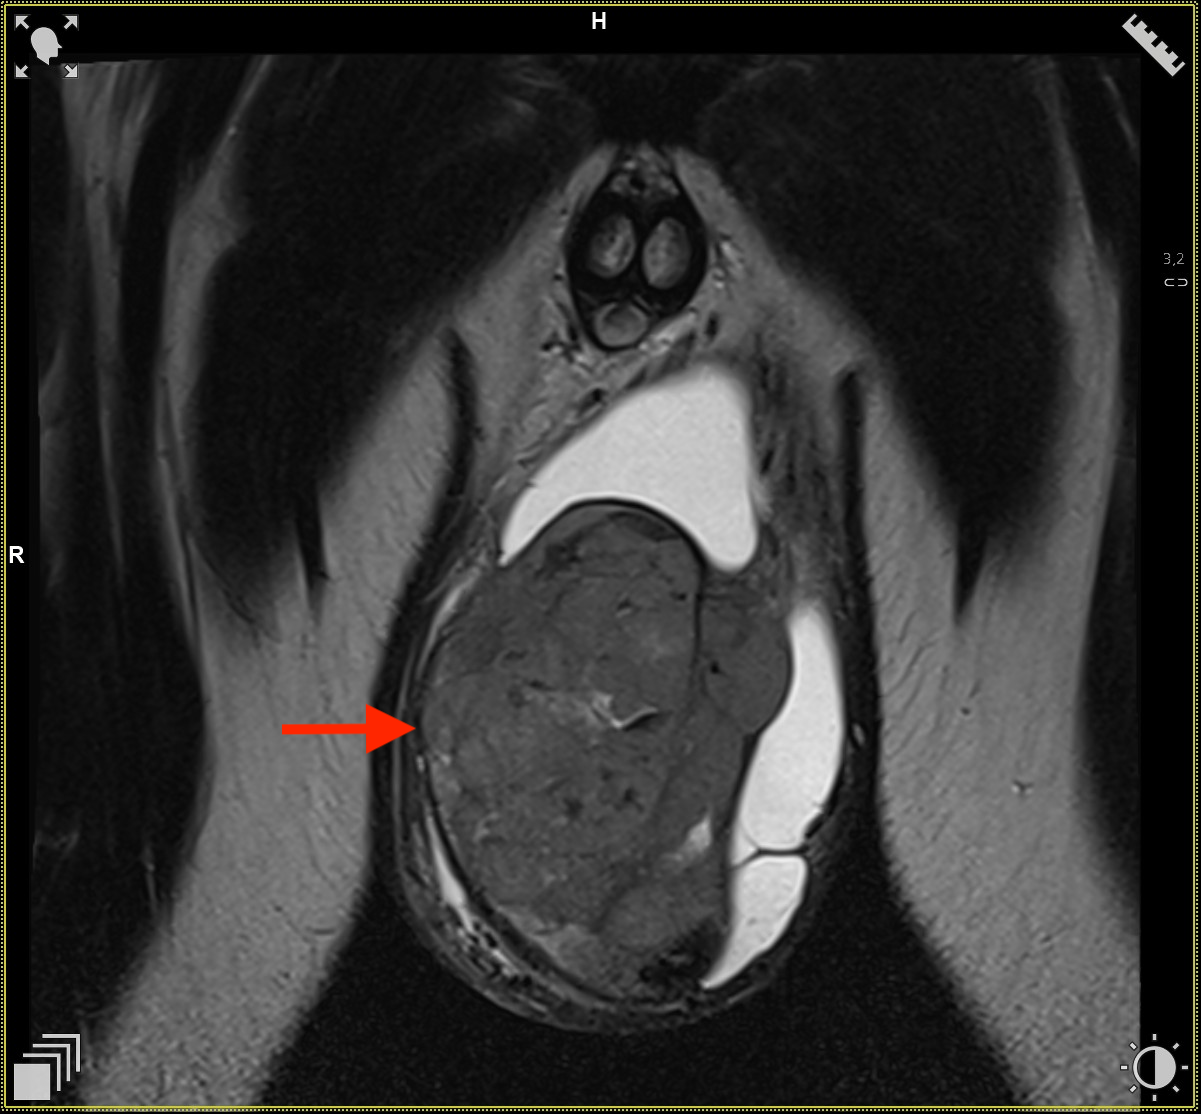

Obrazy w sekwencjach T2 w płaszczyźnie strzałkowej. Widoczna zmiana w jądrze lewym.

Obrazy w sekwencjach T2 w płaszczyźnie osiowej. Widoczna zmiana w jądrze lewym.